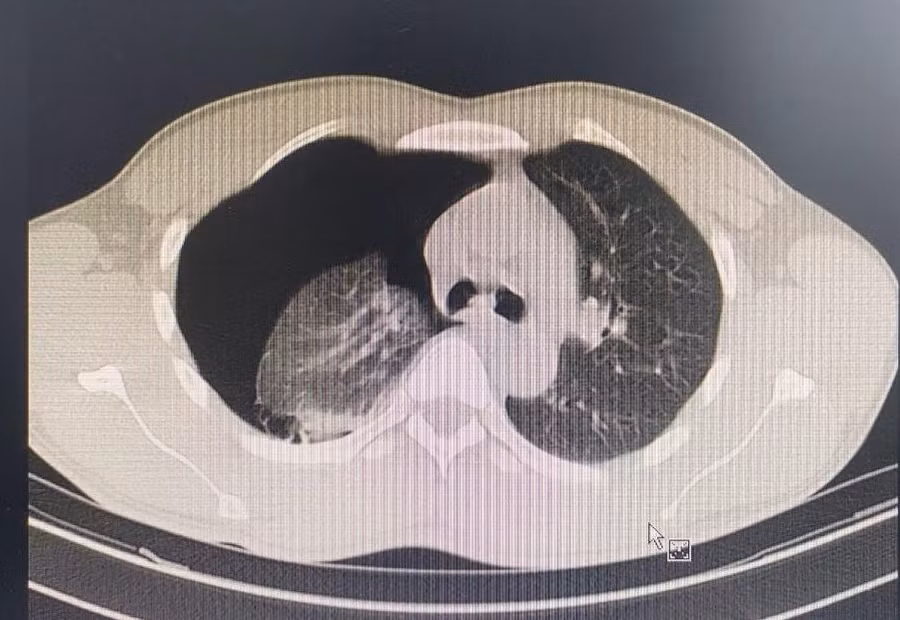

Kết quả Phim CT nhu mô phổi bị xẹp do tràn khí màng phổi. Ảnh: BVCC.

Bệnh nhân được đưa vào Bệnh viện Đa khoa Đức Giang. Qua thăm khám, các bác sĩ nhận thấy, hình ảnh phim Xquang của bệnh nhân có dịch, có khí. Sau khi loại trừ khả năng do dịch bệnh, bệnh nhân được chuyển tới khoa Ngoại tổng hợp.

Các bác sĩ chẩn đoán bệnh nhân bị tràn khí màng phổi tự phát, được chỉ định dẫn lưu màng phổi cấp cứu, mổ khâu kén khí và cầm máu, làm sạch khoang màng phổi. Sau mổ, tình trạng bệnh nhân ổn định, sớm được ra viện.